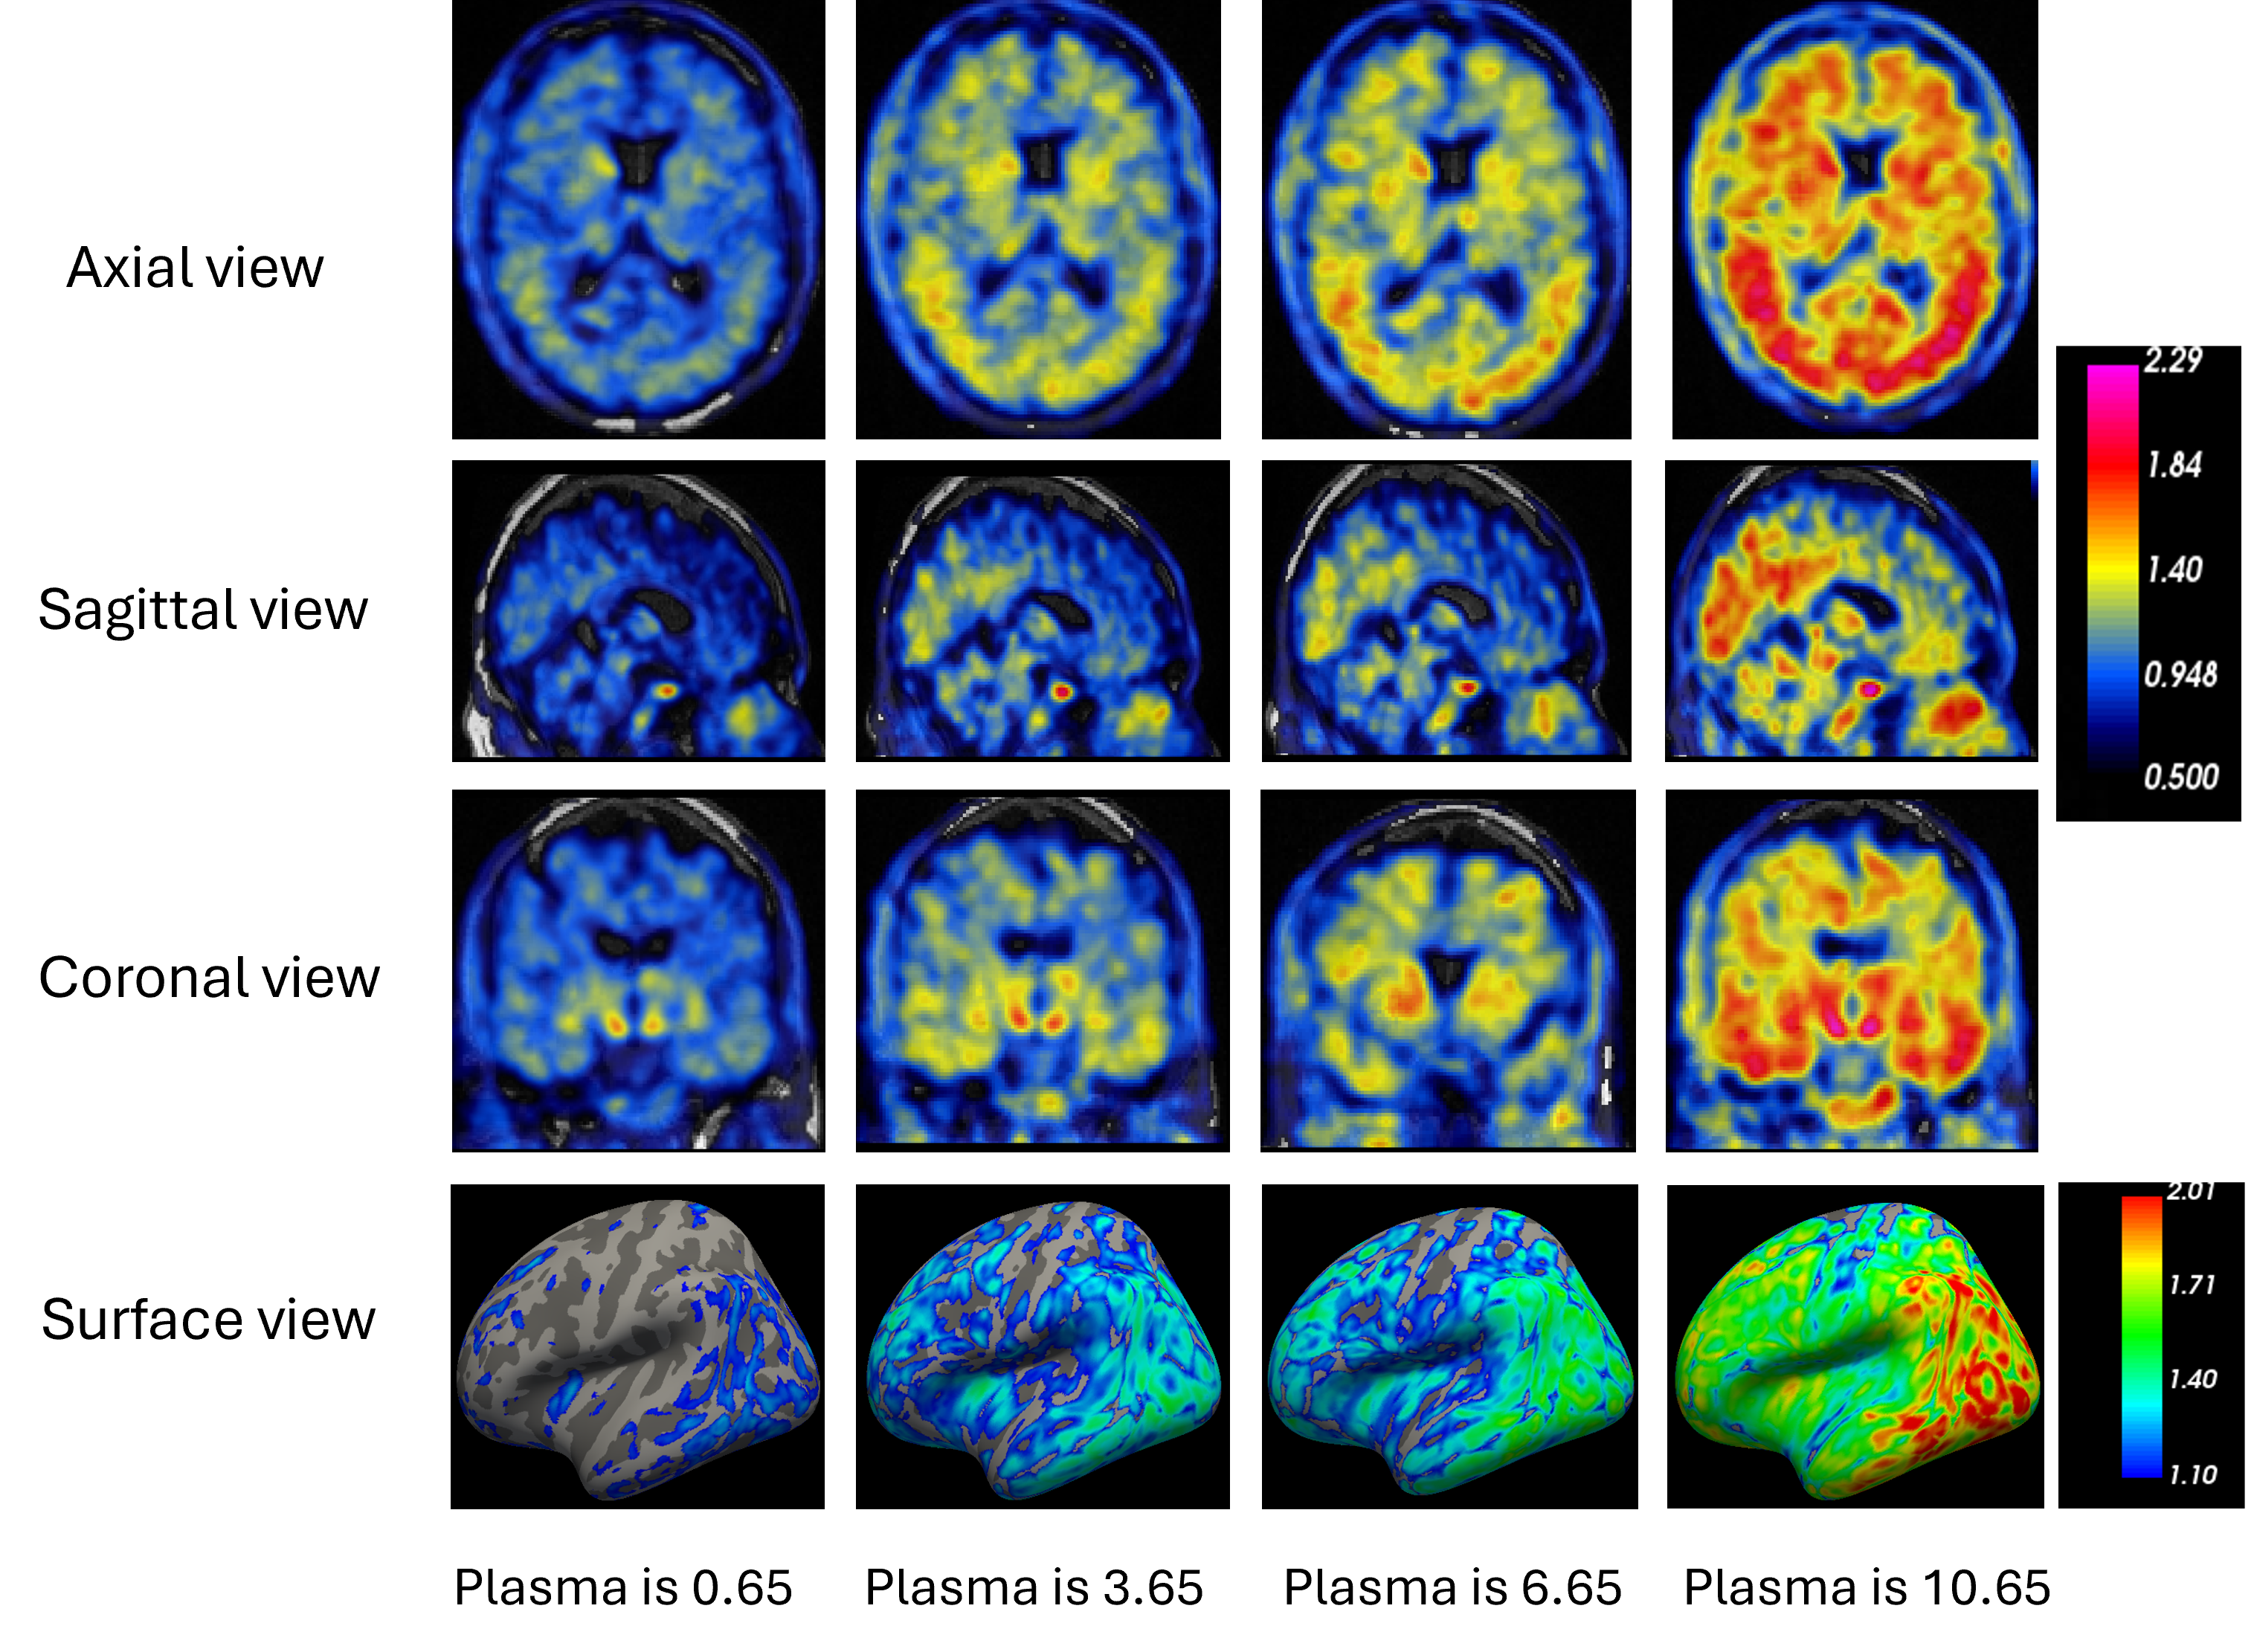

Refer to caption

Figure 2: One example of generated tau PET images across varying p-tau 217 concentrations (0.65, 3.65, 6.65, and 10.65) shown at axial, sagittal, and coronal views (top three rows). The last rows show the surface images at the corresponding p-tau 217 values.

Figure 2 shows an example of the generated tau PET images across varying p-tau 217 values (0.65 to 10.65) while maintaining fixed structural MRI information. The visualization shows that the generated tau PET images exhibit a progressive increase in tracer uptake intensity and spatial extent with increasing plasma biomarker concentrations. At lower plasma values, tau signals are predominantly localized to early tau-related structures, while higher concentrations show expansion into widespread cortical regions. This progression pattern aligns with established tau pathology spread in AD, suggesting the proposed generative model might be able to capture the spatial-temporal relationship between plasma biomarkers and brain pathology.